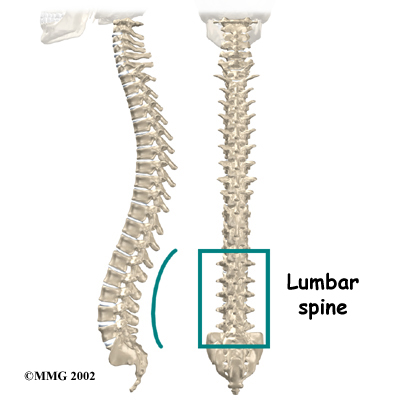

The human spine is made up of 24 spinal bones, called vertebrae. Vertebrae are stacked on top of one another to create the . The spinal column gives the body its form. It is the body's main upright support. The section of the spine in the lower back is called the lumbar spine.

The lumbar spine is made of the lower five vertebrae. Doctors often refer to these vertebrae as L1 to L5. These five vertebrae line up to give the low back a slight inward curve. The of the lumbar spine, L5, connects to the top of the sacrum, a triangular bone at the base of the spine that fits between the two pelvic bones.